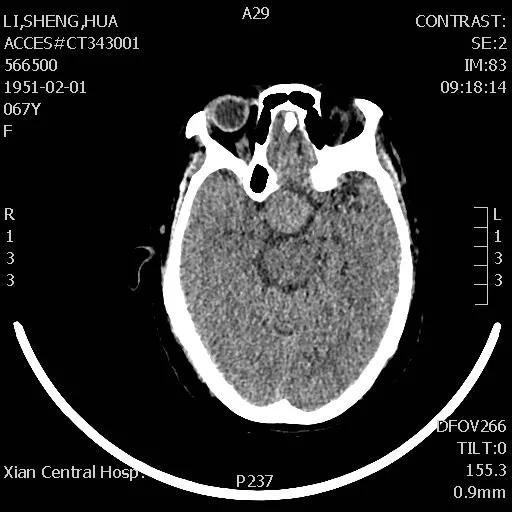

李女士头痛一年多,近日头痛加重并伴有视力迅速下降的症状,经朋友介绍,来到21点玩法研究所 神经外科王占尧主任医师处就诊。王主任通过与病人深切交谈,了解其既往病史、生活习惯、家族病史等后,均未发现有何异常,王占尧主任医师立即成立诊疗小组对李女士的情况进行分析并制定了神经内镜下手术的治疗方案。

手术于次日下午进行,整个过程非常顺利,患者预后也非常理想,术后复查CT显示肿瘤切除干净,患者视力改善明显,经过一段时间的后续治疗,患者已痊愈出院。